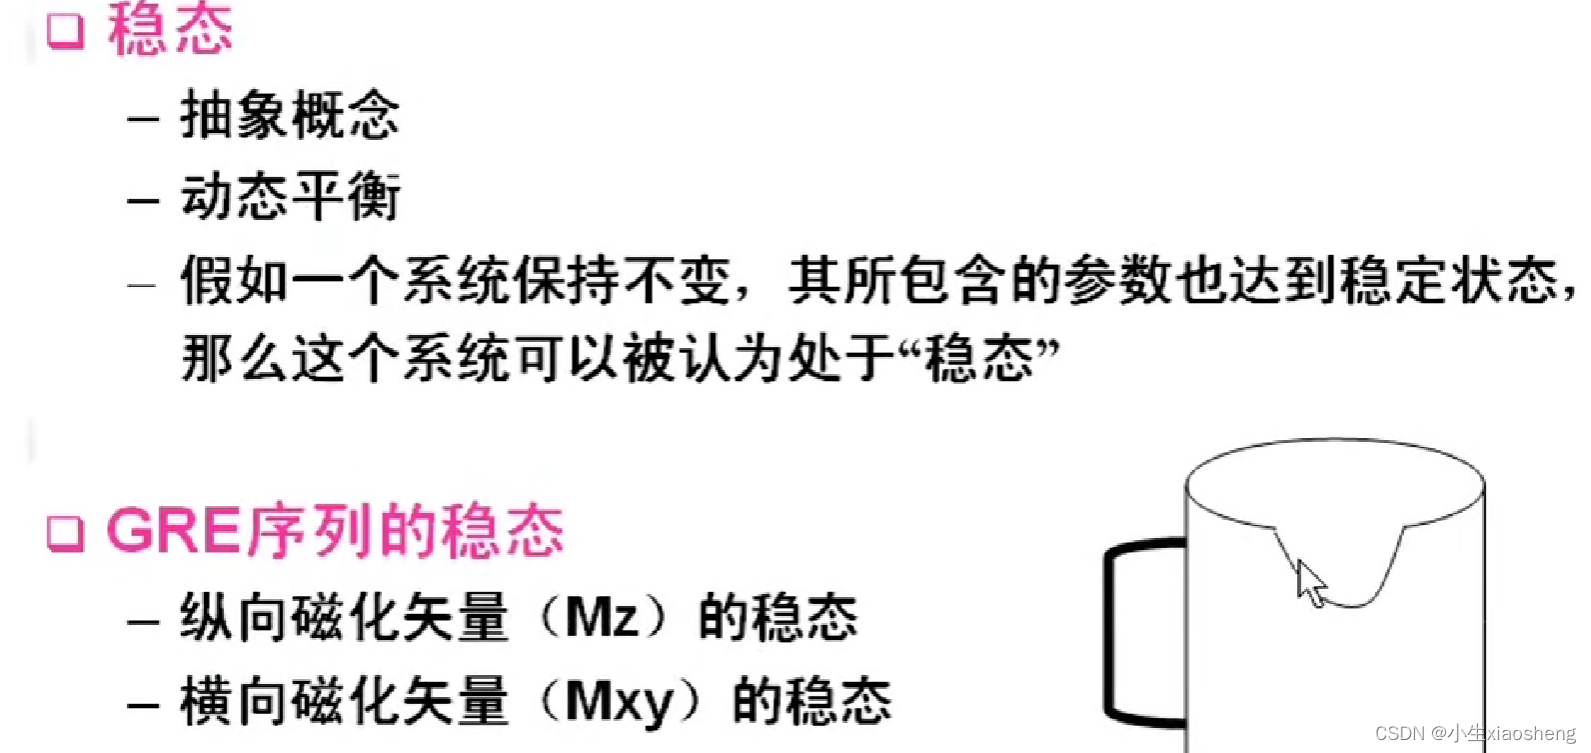

GRE序列中的稳态:流入的和流出的量是一样的,那么容器中的数据一直都是一样的。